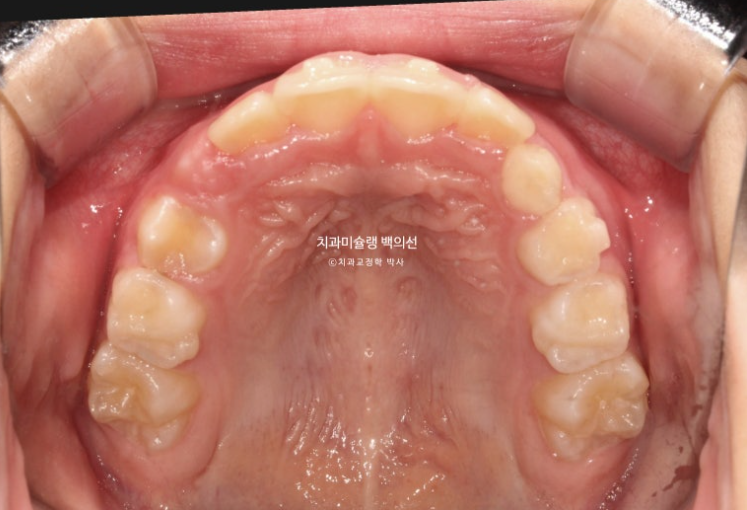

23.06

2년 전 교정치료를 위해 내원한 만 8세 어린이입니다.

이제 겨우 유치 앞니가 빠지고 영구치 앞니가 나오는 시기인데

앞니부터 심한 덧니로 내려오니 부모님이 놀라서 오셨습니다.

이 날 자리가 좁으면 치아가 회전된 상태로 나오거나 입천장으로 나오거나 이 친구처럼 덧니로 내려오게 됩니다.